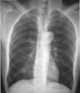

Leukemic infiltrate

A myeloid sarcoma (chloroma, granulocytic sarcoma, extramedullary myeloid tumor), is a solid tumor composed of immature white blood cells called myeloblasts. A chloroma is an extramedullary manifestation of acute myeloid leukemia; in other words, it is a solid collection of leukemic cells occurring outside of the bone marrow. [Source: Wikipedia ]